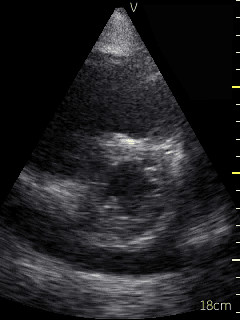

Video 1 (online supplement; Figure 1) demonstrates a parasternal long axis view with the pericardial effusion noted to be posterior to the left ventricle in this view. Video 2 (online supplement; Figure 2) is a short axis view of the heart which is showing that the effusion is surrounding the heart. Video 3 and 4 (online supplements; Figures 3 & 4) demonstrates that the pericardial effusion is present significantly surrounding the apex as well. An echocardiogram confirmed the POCUS findings and cardiology was consulted to conduct a pericardiocentesis, following which the patient’s symptoms resolved. The effusion was thought to be chronic and transudative. In this case, the use of POCUS at the bedside allowed for rapid detection of a large pericardial effusion and subsequent treatment.